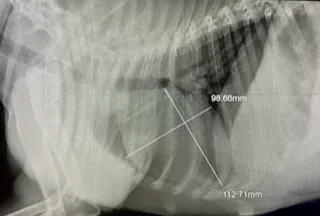

Ordinace je vybavena moderními přístroji, které umožňují rychlou diagnostiku a včasné zahájení léčby přímo na místě.

Abychom zjistili příčinu onemocnění, důležitou součástí je odběr krve a její vyšetření v NAŠÍ laboratoři. Pokud je nutné provádíme sonografické a/nebo rentgenologické vyšetření.